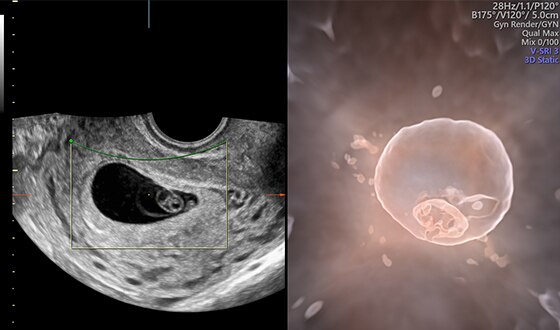

HD𝘭𝘪𝘷𝘦

Семейство технологий Voluson для глубинного понимания анатомии и дифференцировки структур в объеме с беспрецедентной реалистичностью.